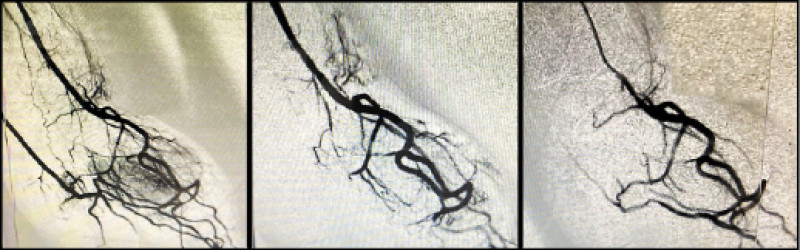

員榮心導室主任林彤宥表示,臨床經驗顯示,這項療法過程與心導管、腫瘤栓塞治療類似,醫師會從手腕橈動脈或鼠蹊部股動脈進行穿刺,在X光透視下導引微導管,將栓塞劑或微球材料注入異常血管,使周邊異常神經因血流受阻而降低活性,減少疼痛訊號傳導,手術之後的影像顯示,原本「雲霧狀」的血管明顯減少,患者疼痛也隨之改善。